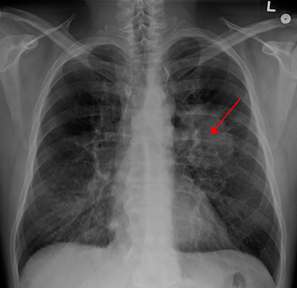

非小细胞肺癌占所有肺癌的87%,约5%的非小细胞肺癌是ALK阳性。ALK阳性肺癌与吸烟无关,是一种非常具有侵袭性的肺癌。

目前第一代和第二代ALK抑制剂都研发出来了,包括克唑替尼、阿来替尼和brigatinib,这些药物非常有效,但患者最终会复发。而且,接受这类药物治疗的患者仍会出现脑转移。

Lorlatinib属于第三代ALK抑制剂,在抑制ALK方面更为有效。目前被美国FDA批准用于前两代ALK抑制剂治疗后疾病仍然进展的ALK阳性患者。

结果非常振奋人心。与克唑替尼组相比,lorlatinib组疾病进展或死亡风险降低了72%。更重要的是,Lorlatinib也将患者出现新的脑转或脑转复发的风险降低了93%。